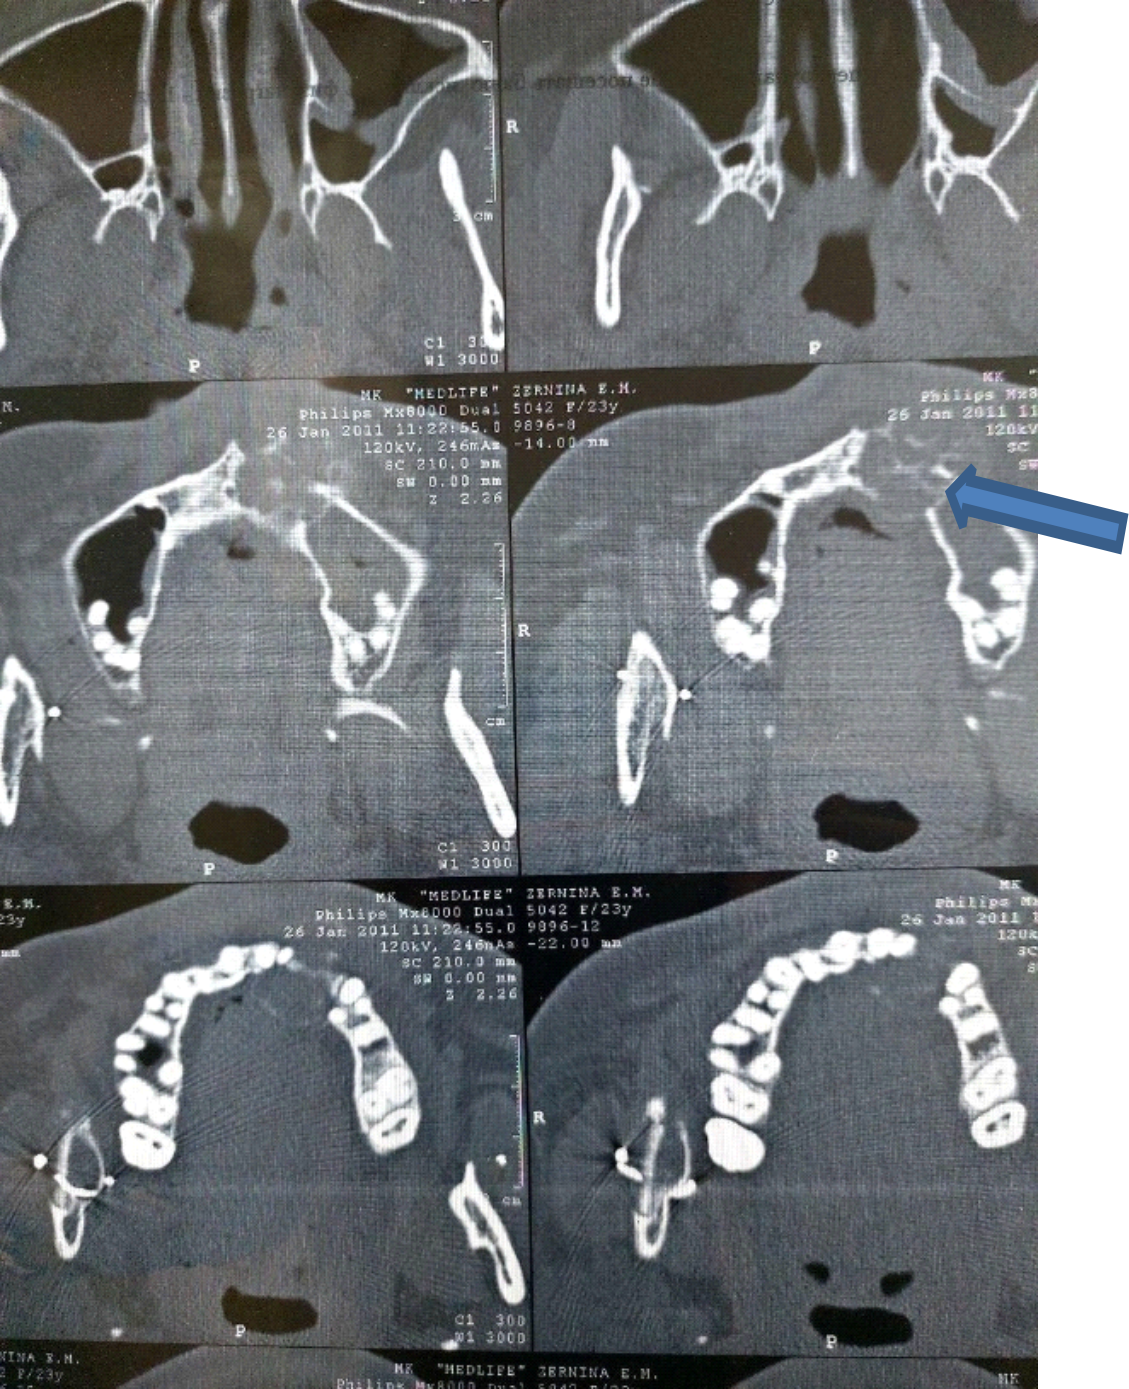

After receiving the results of an incisional biopsy, a diagnosis of osteoclastoma of the frontal maxilla was established (ICD 10 code – D16.4). A resection dentofacial prosthesis for the upper jaw was made according to the defined boundaries of the partial resection of the upper jaw. Surgical treatment was performed – removal of a neoplasm in the area of the frontal part of the upper jaw on the left with partial resection of the upper jaw, with closure of the surgical wound with a flap from the mucous membrane of the cheek and one-stage replacement of the defect with a resection prosthesis. In the postoperative period, a course of anti-inflammatory therapy was administered. As a result of additional examination, a control CBCT scan revealed a neoplasm in the frontal part of the lower jaw on the right side from the lingual side. An incisional biopsy was performed. The diagnosis was established: D16.5 – osteoclastoma of the lower jaw on the right, relapse (Fig. 5), confirmed by the results of pathohistological examination.

Fig. 5. CBCT: osteoclastoma of the lower jaw on the right, relapse, 2011

Due to the presence of a polyostotic form of osteoclastoma of the jaw bones in the patient, autotransplantation was contraindicated. After conducting an anthropometric study and selecting an orthotopic carbon implant, the neoplasm was removed with partial resection of the chin section of the lower jaw and replacement of the carbon orthotopic implant of the lower jaw "Uglekon-M" with a new one.

During the surgical intervention, complete osseointegration was revealed and formation of a bone-implant unit with the ingrowth of bone tissue into the structures of the implant made of carbon-carbon composite material (Fig. 6).